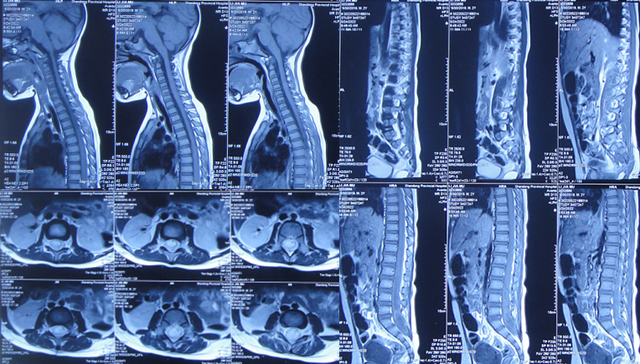

在第2家医院治疗13天即2022年5月24日,患儿仍间断高热,在医生建议下当天转至上级的第3家医院山东省某省级三甲医院,查脊髓核磁(图-2)后行腰椎穿刺有脓液吸出,给予腰大池置管术,但未见脑脊液流出,给予消炎、营养脑神经治疗。

图-2:2022年5月24日脊髓核磁

该院治疗11天期间,体温变正常,期间两次查脊髓核磁(图-4、图-5)示脊髓栓系松解术后。

图-4:2022年6月23日脊髓核磁

图-5:2022年6月28日脊髓核磁